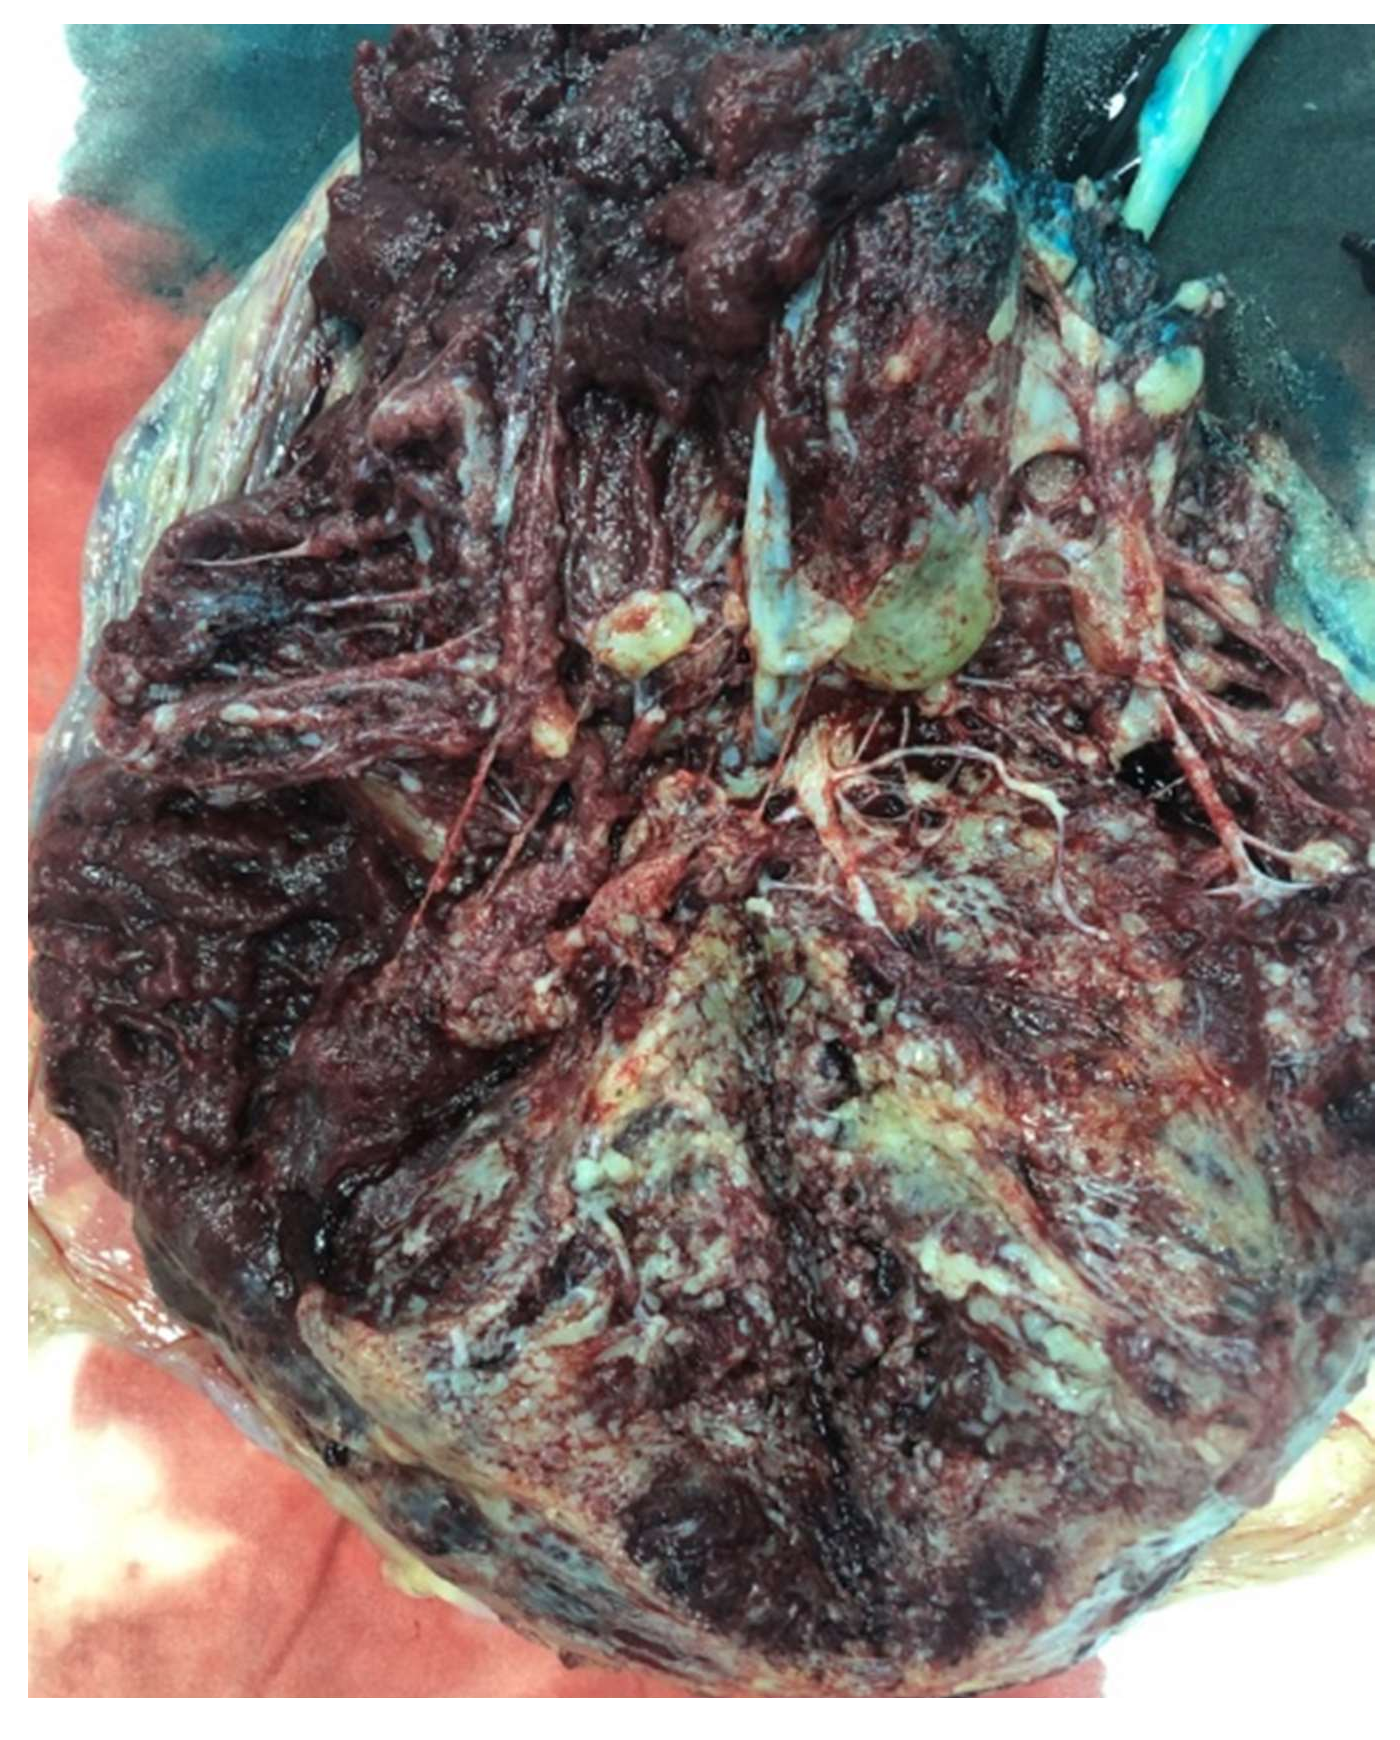

3. Case Report